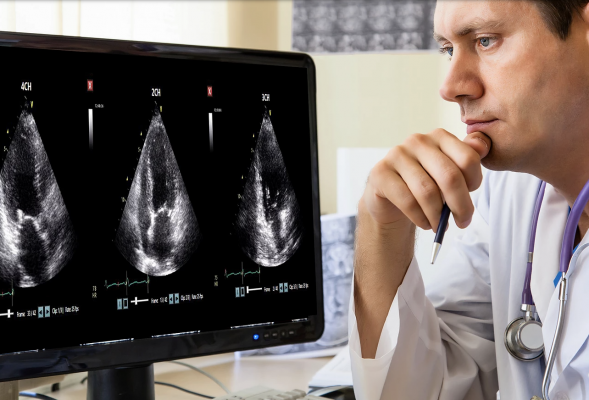

October 29. 2020 — DiA Imaging Analysis announced today that it has received 510(k) clearance from the U.S. Food and Drug Administration (FDA) for the commercial use of LVivo Seamless for automatic view selection. LVivo Seamless algorithms automatically run "behind the scenes" to select the optimal cardiac ultrasound views out of 40-60 views in standard echocardiogram exams. Finding the right views in each echo exam is cumbersome and time-consuming. The ability to auto-select views is a breakthrough in AI implementation and the value that it brings to the echocardiography workflow.

"LVivo software operates without human touch, and adds great value," says Steve Feinstein, M.D., professor of cardiology at Rush University Medical Center. "These rapid, reliable and accurate serial views selections and measurements enable us to get second opinions and access anytime and anywhere."

The cleared LVivo Seamless solution integrates with DiA's other LVivo cardiac auto analysis toolbox products such as LVivo EF, an automated calculation of ejection fraction (EF) calculation, which is a main indicator of global heart function.

This enables clinicians to automatically obtain, for each echo-lab cardiac exam, optimal views and automated measurements in a fast, accurate and objective way.